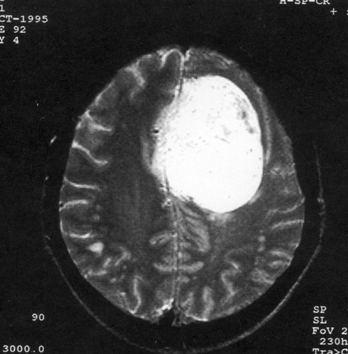

问题 病历摘要:??患者,男,40岁。发作性左下肢抽搐1年余,每次发作3~5分,每周发作1~2次。每次发作后感左下肢乏力,约半日后可自行恢复。既往身体健康。体检:神清,头顶部偏右有局限性骨性隆起(1.5×1.5cm),左鼻唇沟稍浅,伸舌居中。感觉、运动无明显异常。左浅反射减退,左下肢腱反射稍亢进,左Babinski征(-)。 下列对该患者的临床特点分析哪些是正确的?

选项 A.有Jackson癫痫发作 B.有Todd氏麻痹 C.有精神运动性癫痫发作 D.右中央前回可能有刺激性病灶存在 E.右中央后回可能有破坏性病灶存在 F.有失张力发作 G.右锥体束征(+) H.有颅内高压表现

答案 ABDG

解析 ABDG